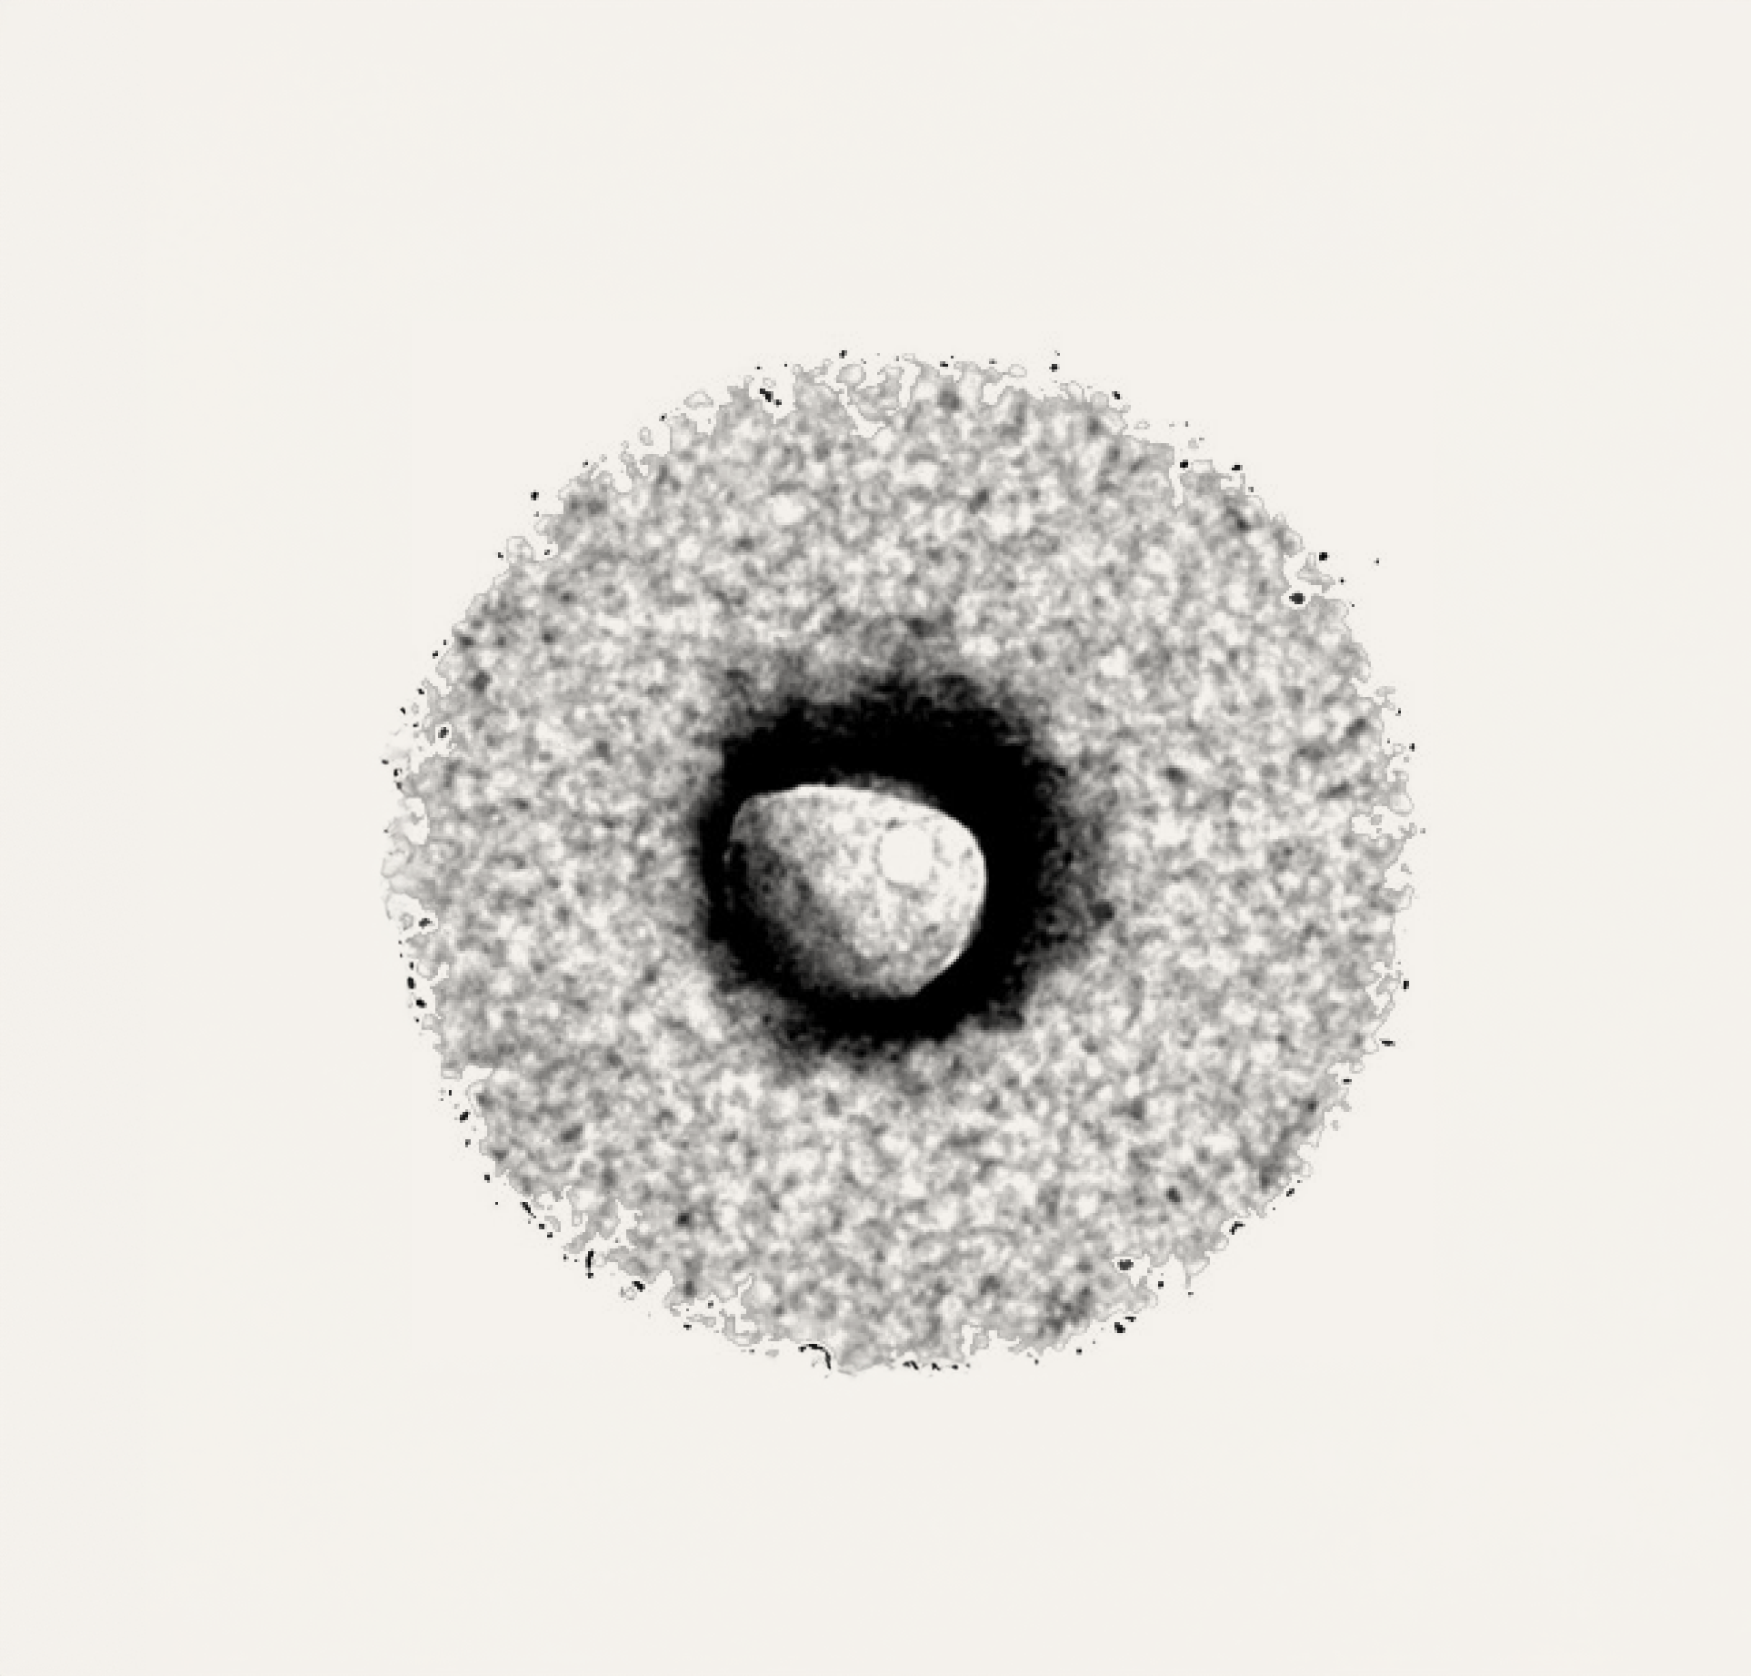

Liposomes are tiny spherical vesicles composed of lipid bilayers, which can encapsulate both water-soluble and fat-soluble substances. This unique delivery system is designed to enhance the absorption and bioavailability of the encapsulated ingredients.

Figure: Cryogenic transmission electron microscopy (TEM) image of a liposomal sphere (Joungbo et al. 2023).